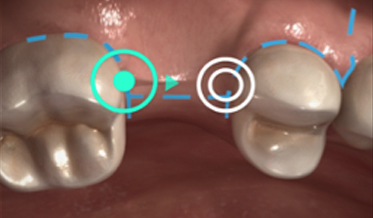

Immediate Implant Placement, Immediate Load With Same-Day Fully Digital Fabrication of a Screw-Retained Provisional Implant Prosthesis